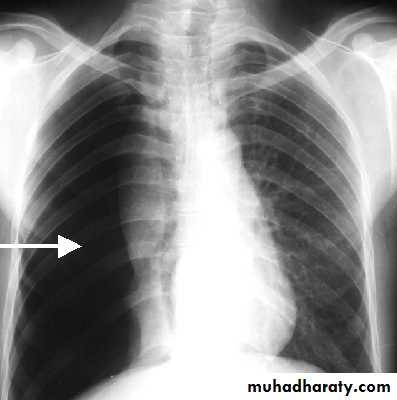

Commonest symptoms are sudden-onset unilateral pleuritic chest pain or breathlessnessSmall pneumothorax (<2 cm visible rim of air on chest x ray between lung margin and chest wall and occupying <50% of the volume of hemithorax)

A larger pneumothorax (>2 cm visible rim of air on chest x ray between lung margin and chest wall and occupying >50% of the volume of hemithorax) results in;

Chest X-ray;Shows the sharply defined edge of the deflated lung with complete translucency (no lung markings) between this and the chest wall. Chest X-rays also show the extent of any mediastinal displacement and give information regarding the presence or absence of pleural fluid and underlying pulmonary disease.